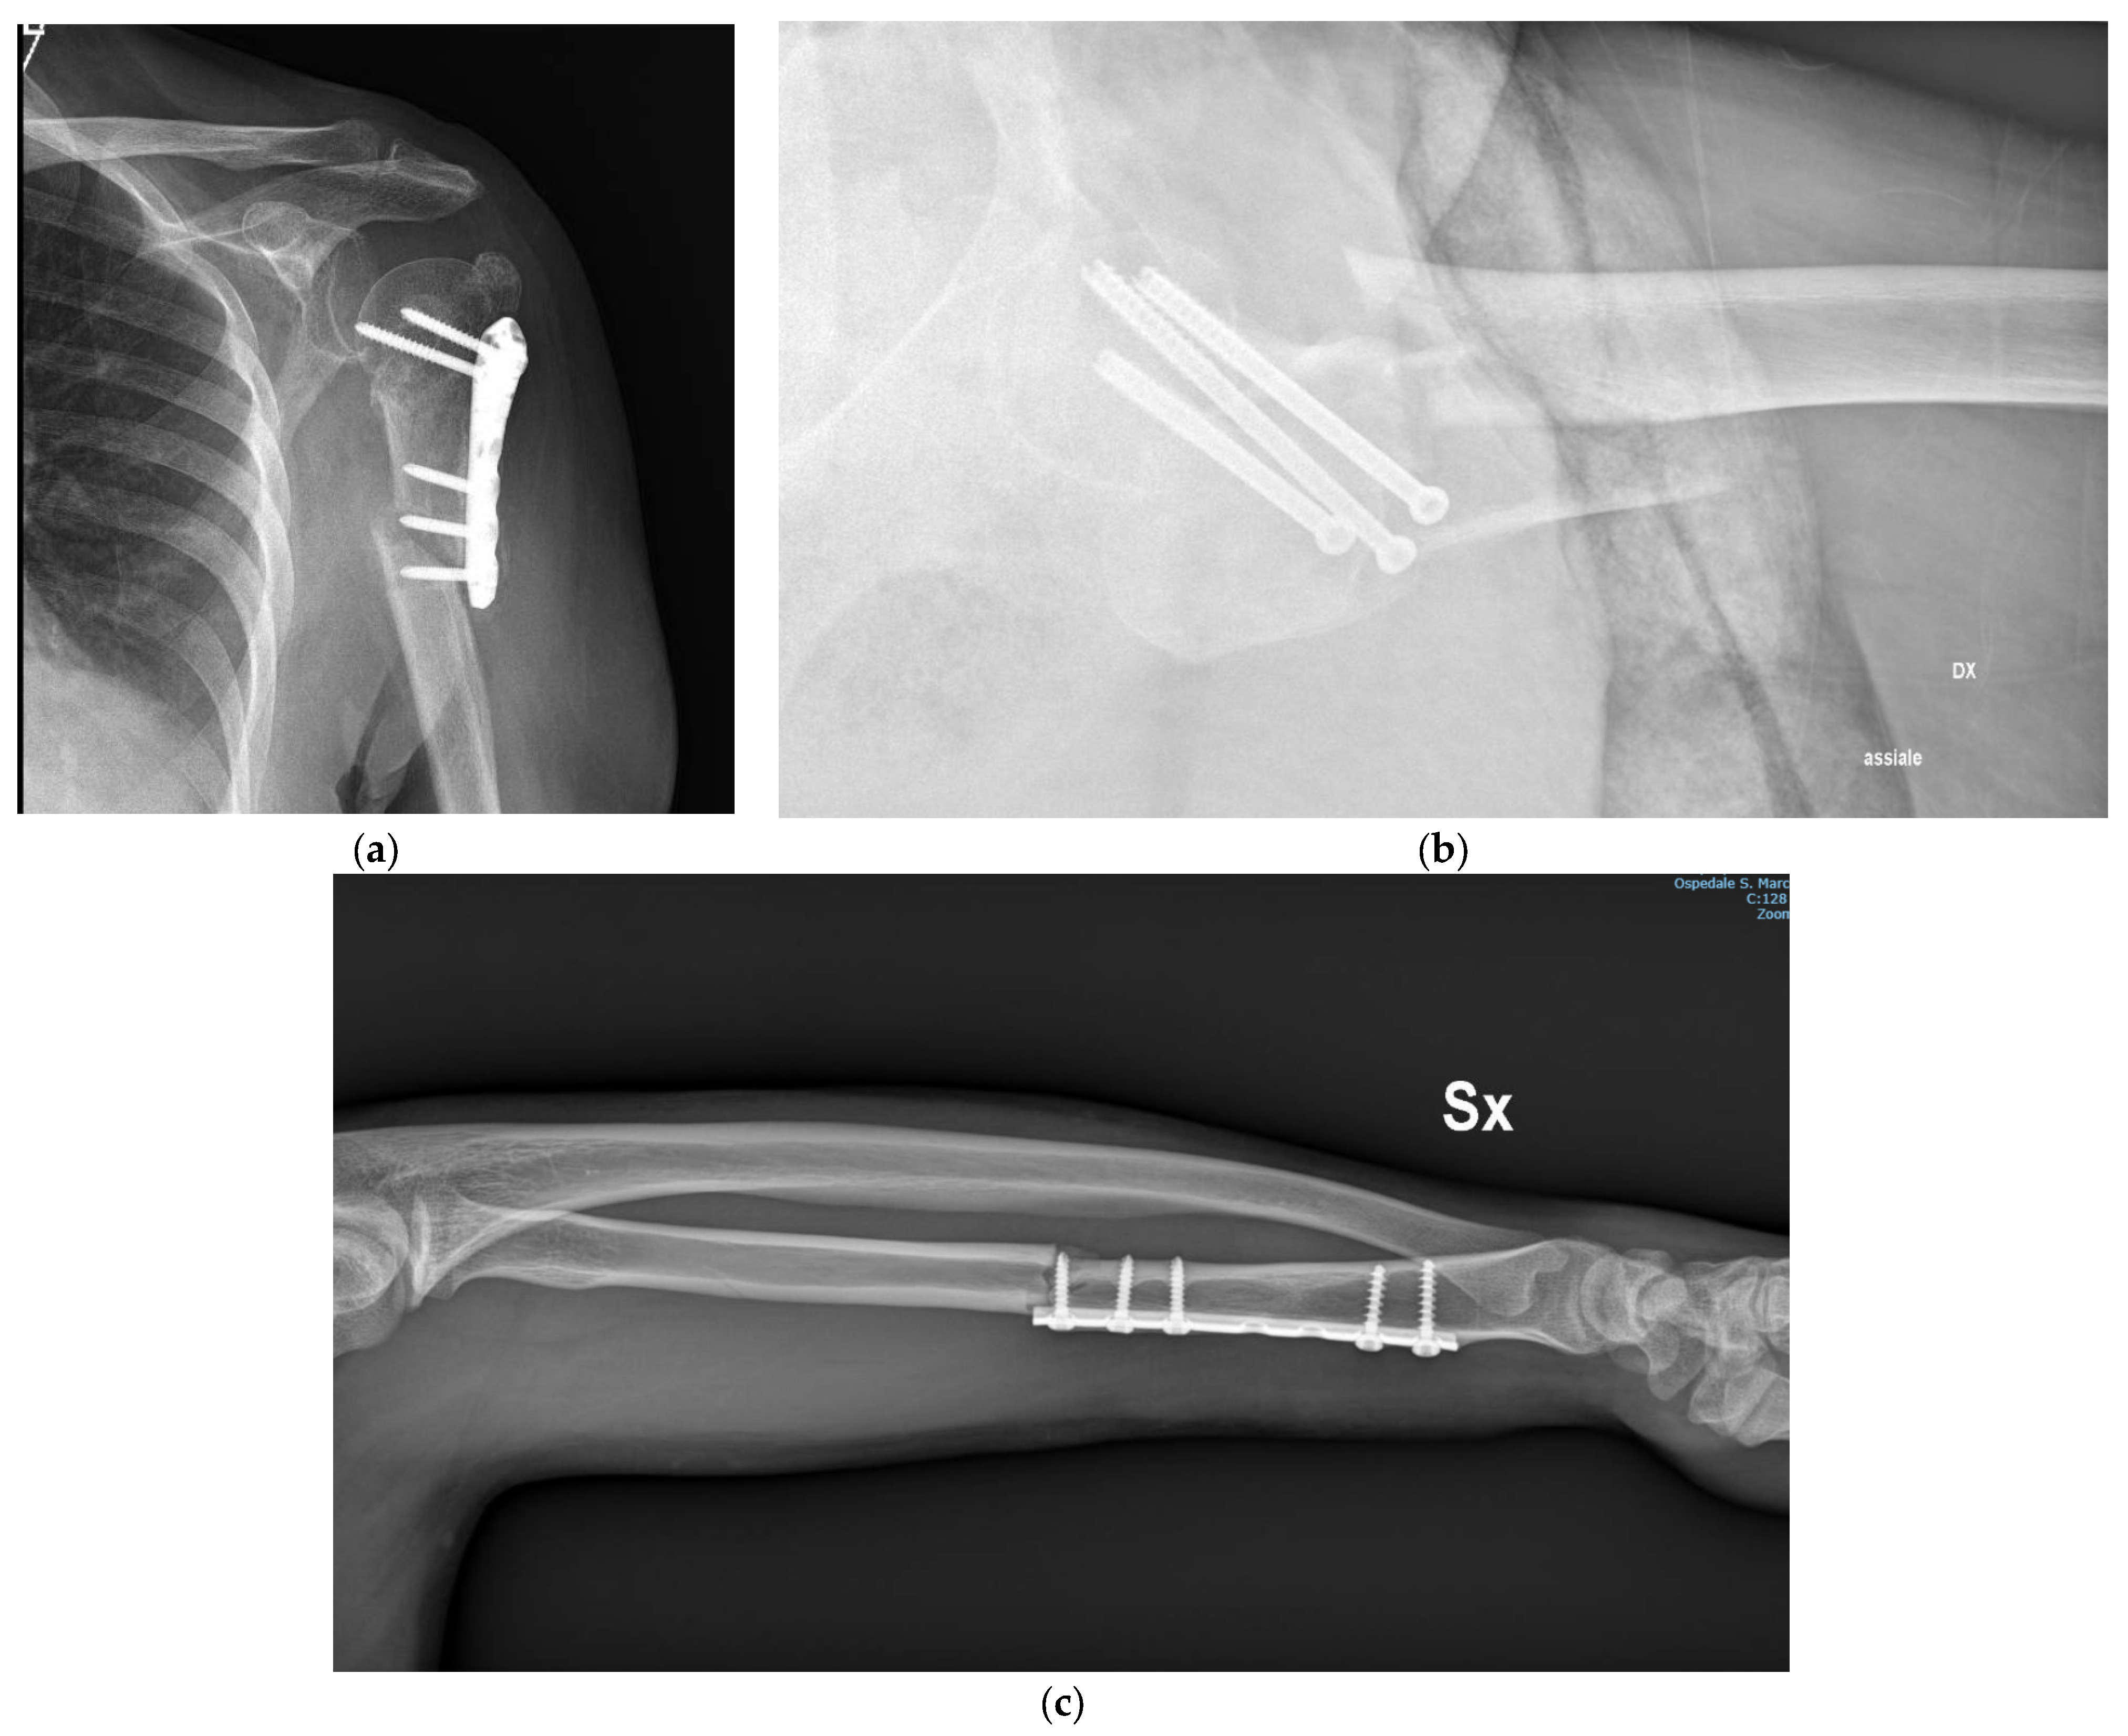

- α: plate and screws;

| Plate and screws | Alfa (α) |